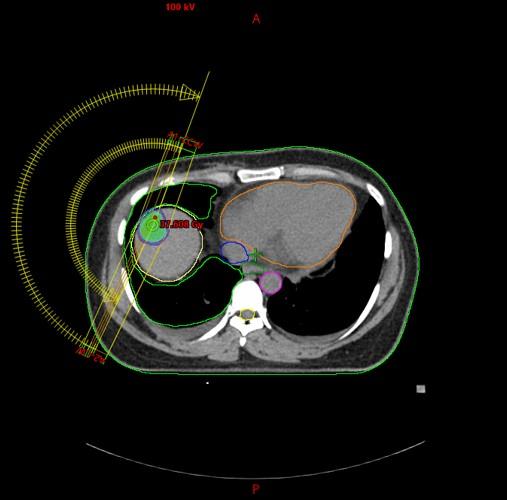

Jetra

Bolesnik, rođen 1971. Dijagnoza: